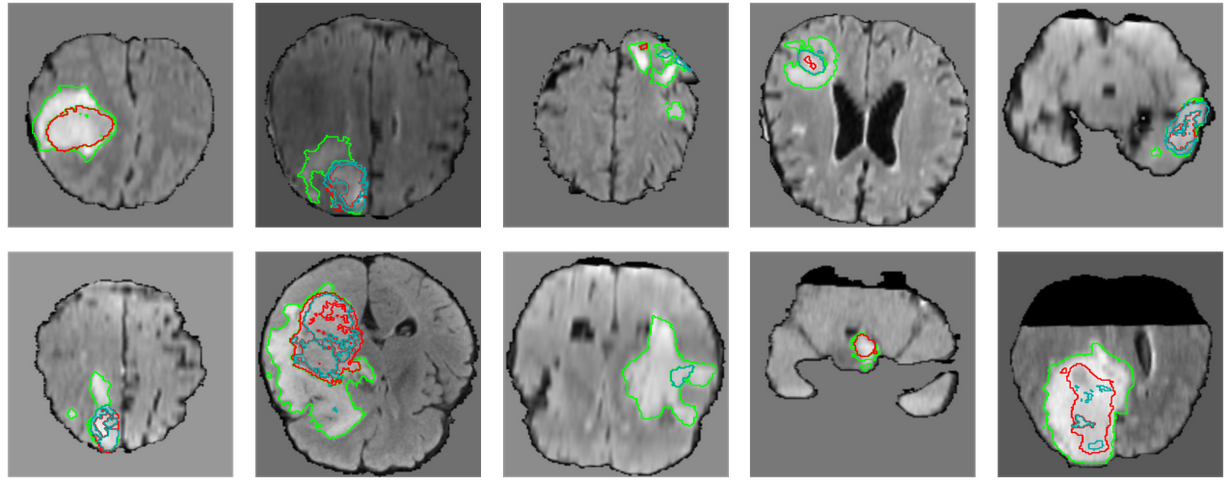

Refer to caption

Figure 9: Slices of images from the Brain Tumour Dataset. Green: edema, Red: non-enhancing tumour, Cyan: enhancing tumour.

The results from the 5-fold experiments and ensembling are presented in Table 4. For comparison with a state-of-the-art model, in Table 4 we provide the results from the 2D network of 7. For visualization, we followed the same approach as on the Cervical Cancer Dataset to find the fold with the median performance of the models. Then we randomly selected 3 patients from the validation set of this fold, from which we selected 1 slice based on the reference with enough information. In Figure 10 we illustrate the predictions of the models on these 3 patients, where again we observe a high overlap between them, but at the same time every model makes different mistakes. We also calculated the Dice score between predictions of pairs of models (Table 5), and again observed a very high similarity (in most cases except those involving the UNETR model, the models achieve more than 0.84 Dice score).

Figure 10: Predictions of models on the Brain Tumour Dataset. Green: edema, Red: non-enhancing tumour, Cyan: enhancing tumour.